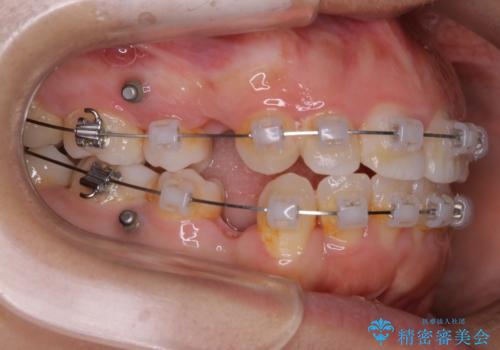

- 矯正装置

- ワイヤー(クリア装置)

- 治療計画

- 口元を下げたいという主訴でご来院されました。

ガタつきの度合いは軽度でしたが歯列の幅が狭く、その分前歯が上下とも前方に出てしまっていました。

しっかりと口元・顔貌まで変化を起こせるように上下左右の第一小臼歯を抜歯し、ワイヤー装置にて矯正を開始することとなりました。